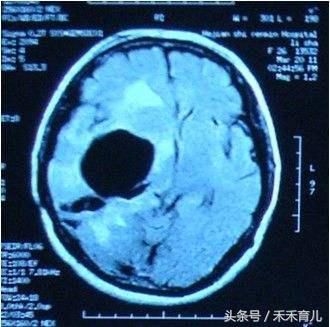

首先给大家说下脑侧室增宽的定义:侧脑室宽度是预测胎儿神经系统功能的一项重要指标,因此是产前系统超声检查的常规项目;在妊娠16-38周内,正常的侧脑室宽度一般为7.6mm±0.6mm,当胎儿侧脑室体部宽度达10~15mm,称为轻度侧脑室增宽,在中晚孕期发生率约1%;若胎儿轻度侧脑室增宽未合并其他任何结构异常时则称为孤立性轻度侧脑室增宽;若侧脑室宽度超过15mm则为胎儿脑积水;约60%的病例为单侧轻度侧脑室增宽,约40%的病例为双侧轻度侧脑室增宽。

脑侧室多宽才算宽

1、10~12毫米,轻度侧脑室增宽;

2、12~15毫米,中度侧脑室增宽;

3、15毫米以上,重度侧脑室增宽。而这种重度侧脑室增宽,就是我们白话说的脑积水。

因为侧脑室增宽有轻度、中度、重度之分,因此孩子的恢复情况也不一样。现在我们倾向于将10~12毫米的侧脑室增宽叫做临界增宽。现在发现80%以上有轻度侧脑室增宽的胎儿,出生之后是正常的。 但也有一些轻度增宽的胎儿定期检查发现,侧脑室的宽度在逐渐增加,比如这次查11~12毫米,2~3周再查时发展到13~14毫米了,再复查发现变成14~15毫米。这种情况可能预示着孩子出生之后存在神经系统和智力的损伤。 当然,无论是逐渐增宽到15毫米以上,还是第一次检查就在15毫米以上,最后的恢复都是比较差的。如果大脑里的水多了,可供大脑发育的空间也就相应减少。所以如果侧脑室达到15毫米以上的脑积水标准,就会把脑子压得比较扁,进而对孩子的神经发育造成影响。